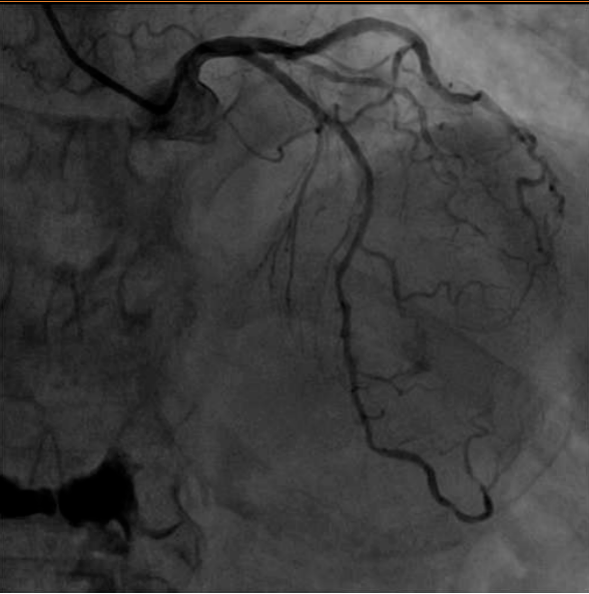

手术当天 , 李大娘顺利完成了冠脉造影检查 。 造影见左侧冠脉有很多斑块 , 但血管管腔狭窄尚不严重 。 右冠多处节段性狭窄 , 其中远段后侧支可见80%狭窄 。

看到这样的造影结果 , 大家都松了一口气 。 李大娘的确是因为右冠脉狭窄导致了下壁心肌梗死 , 但结合入院以来完善的血清学指标 , 已属陈旧性心肌梗死 。

造影见右冠脉远段仍有80%狭窄 , 属于临界病变 , 可先通过系统药物治疗来达到骨科围术期预防心脏风险的目的 。 目前可优先进行骨科手术治疗 。